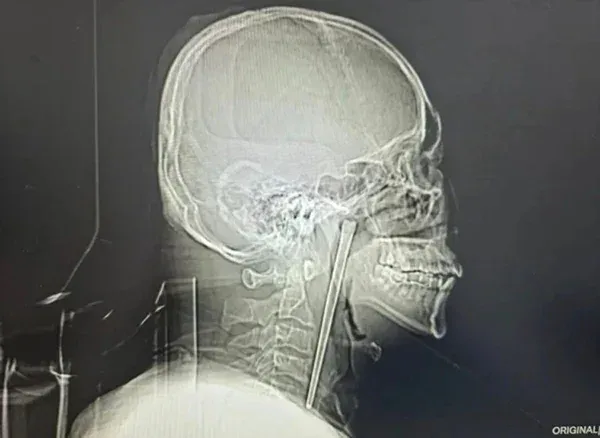

กลายเป็นเรื่องฮือฮาในโลกโซเชียล เมื่อสำนักข่าวต่างประเทศรายงานเหตุการณ์สุดเหลือเชื่อของชายชาวจีนวัย 46 ปี จากเมืองต้าเหลียน ที่ใช้ชีวิตอยู่กับ "ตะเกียบเหล็กยาว 12 เซนติเมตร" ปักอยู่ในลำคอนานถึง 8 ปี เพียงเพราะความกลัวการผ่าตัด จนเกือบเอาชีวิตไม่รอด

ผลการตรวจร่างกายอย่างละเอียดทำเอาทีมแพทย์ต้องตะลึง เมื่อพบ ตะเกียบเหล็กยาวถึง 12 เซนติเมตร ฝังแน่นอยู่ในผนังคอหอยด้านขวา โดยมีส่วนปลายโผล่ออกมาประมาณ 3 เซนติเมตร